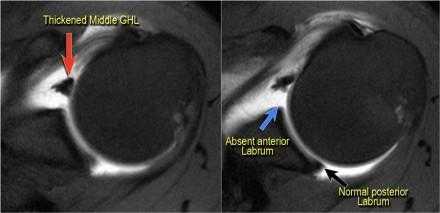

Комплекс Буфорда

Комплекс Буфорда это врожденный вариант строения суставной губы в виде отсутствия ее передневерхних отделов в области на 1-3 часа и утолщение средней плече-лопаточной связки.

Определяется в 1,5 % случаев.

На аксиальных изображениях слева может быть виден комплекс Буфорда.

Отсутствуют переднеие отделы суставной губы в области на 1-3 часв, утолщена средняя плече-лопаточная связка.

Утолщенная средняя плече-лопаточная связка не должна обшибочно приниматься за смещенную суставную губу.

Всегда по возможности необходимо прослеживать ход средней плече-лопаточная связки сверху вниз от фиброзно-хрящевой губы гленоида к плечевой кости.